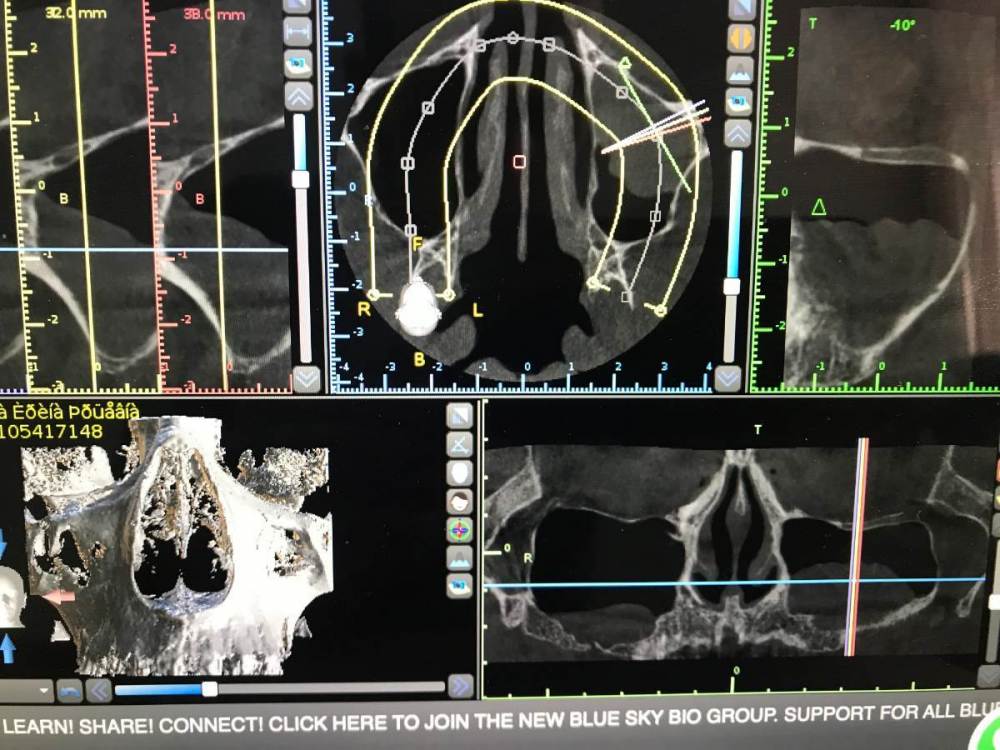

TIGER Опубликовано 18 февраля, 2022 Поделиться Опубликовано 18 февраля, 2022 Приветствую коллеги!Небольшой кейс с удалением кисты и синусом.Произведено :удаление кисты,синус-лифт ,через 4 месяца имплантация,ещё через 4 протезирование 5 1 1 Ссылка на комментарий